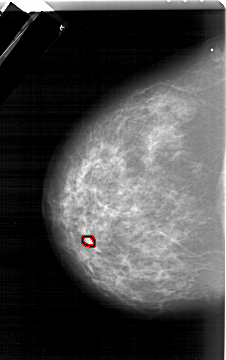

A_1284_1.LEFT_CC

LEFT_CC LINES 6466 PIXELS_PER_LINE 4066 BITS_PER_PIXEL 12 RESOLUTION 43.5 OVERLAY

FILE: A_1284_1.LEFT_CC.OVERLAY

TOTAL_ABNORMALITIES 1

ABNORMALITY 1

LESION_TYPE MASS SHAPE OVAL MARGINS OBSCURED

ASSESSMENT 4

SUBTLETY 3

PATHOLOGY BENIGN

TOTAL_OUTLINES 1

BOUNDARY